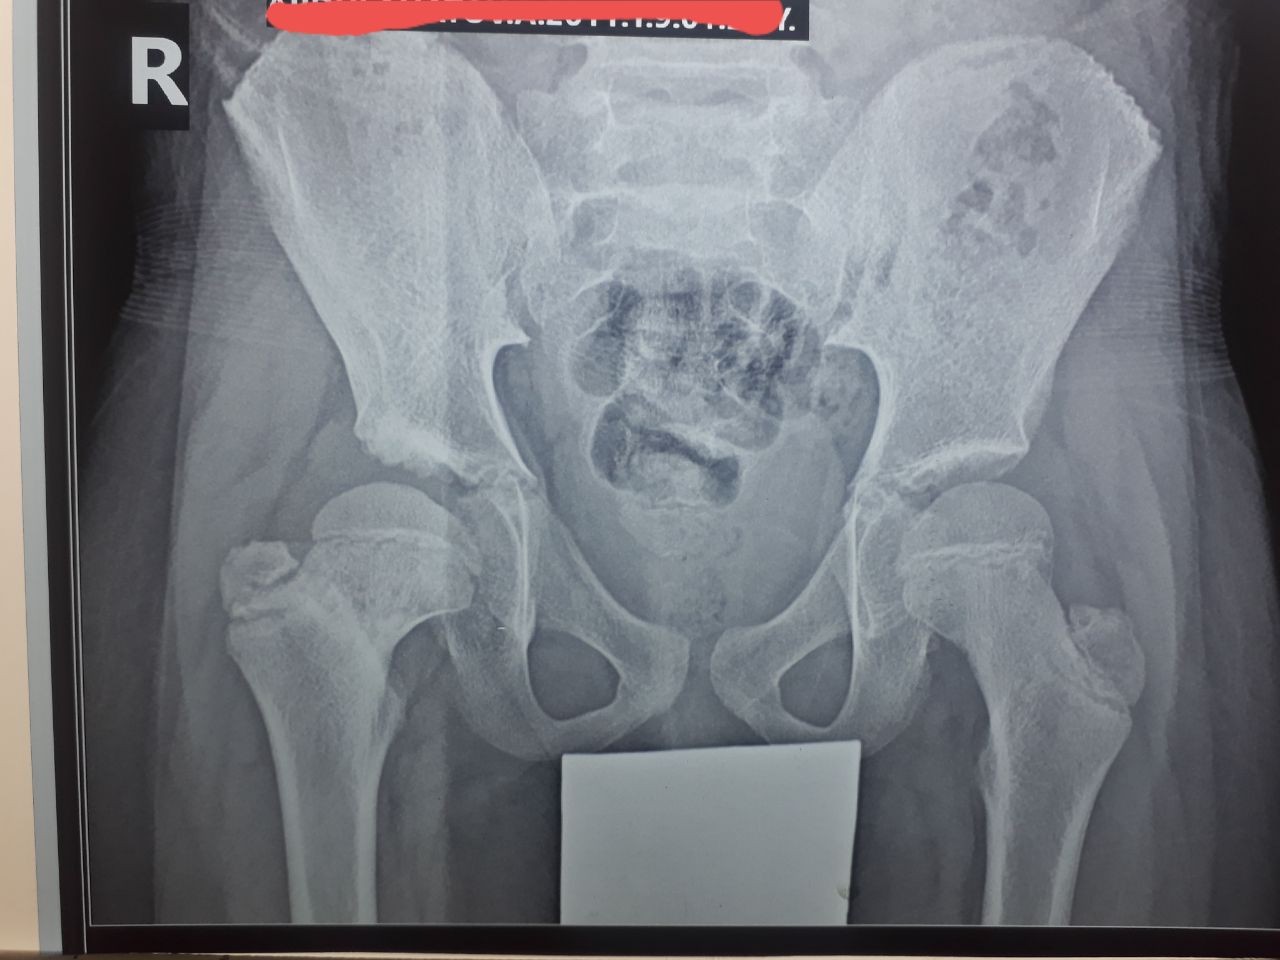

Доброе утро всем! Помогите с описанием пожалуйста!

Elyorbek

Остеохондропатия головки бедренной кости справа

Elyorbek in Radiology/Рентгенология Чат